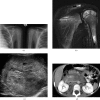

Neuroblastoma is one of the most common malignant neoplasms in childhood. The most common clinical presentation of this tumour is abdominal mass. However, affected children may have various clinical presentations as a result of disseminated metastatic disease or associated paraneoplastic syndromes at the time of diagnosis. In this article we have outlined the imaging findings in seven patients with "extra-abdominal" presentation of neuroblastoma and the pitfalls in making the correct diagnosis. The purpose of this pictorial review is to alert the general radiologist to the possible presentations of this common childhood malignancy to derive early detection and diagnosis.